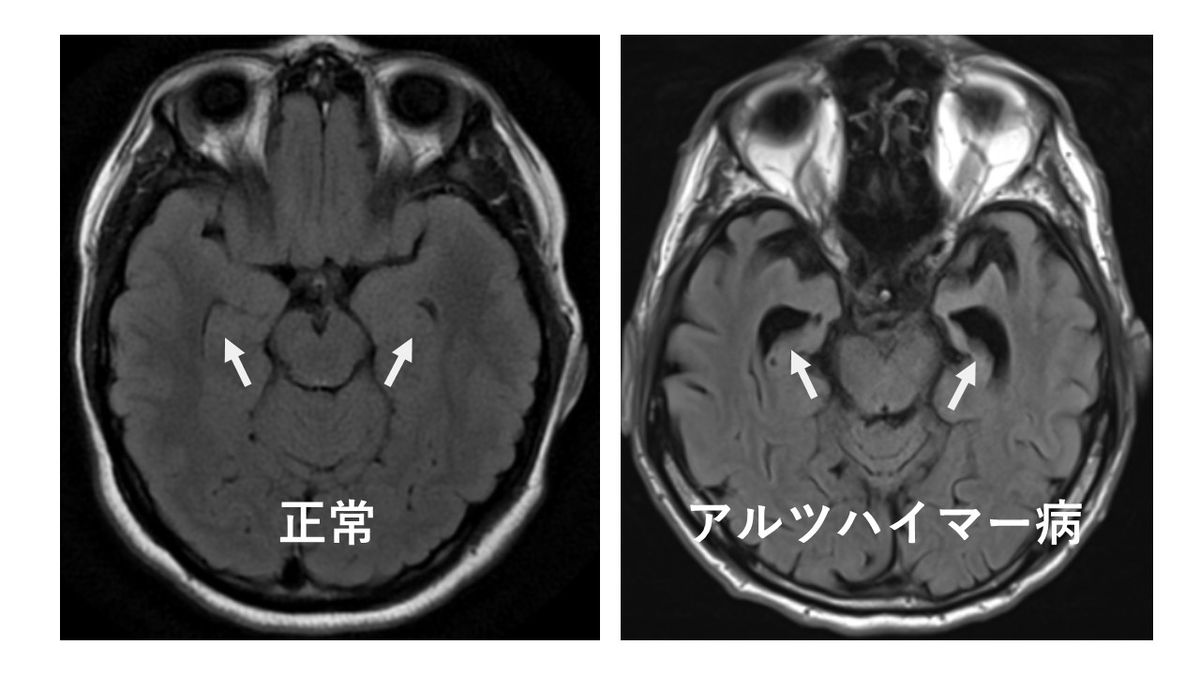

画像診断(MRI・CT)や血液検査の役割

認知症の原因を特定するために、脳の画像診断も行われます。MRIやCT検査で脳の萎縮や血管の状態を確認し、脳梗塞や脳腫瘍といった他の病気の有無を調べます。

また、血液検査では甲状腺機能やビタミン欠乏、感染症など認知症に似た症状を引き起こす可能性のある病気を除外します。これらの検査があるために、病院での診断はより正確で信頼できます。